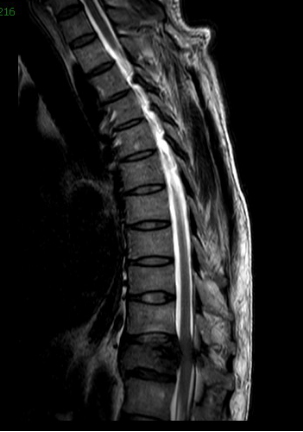

经过慎重考虑,老李决定返乡,并慕名来到我院就诊。脊柱外三科主任陈海龙看到老李的脊柱DR片后,顿感情况不妙,胸11椎体高度降低,椎体骨质及右侧附件结构严重破坏,幸运的是老李目前没有神经损伤症状,否则严重的话可造成双下肢截瘫。陈主任安排医师为老李紧急办理了住院手续,一边叮嘱他绝对卧床,一边加快各项相关检查。结合他的CT及MRI等影像资料显示,结果不过容乐观,不出所料,胸11肿瘤毫无疑问,而后穿刺活检的病理结果再次证实了医生的判断:骨巨细胞瘤。但幸运的是,经过全面彻底排查,未见肿瘤转移,那么此时此刻对老李来讲,完整彻底地切除肿瘤,是最优的选择。

在困难面前,我院脊柱外三科团队没有退缩,在精心策划手术方案后,首先请介入科为老李做了节段血管栓塞,以减少术中出血,而后由陈海龙主任医师主刀,带领主治医师马俊杰、管床医师朱博组成的手术团队,在麻醉医师紧密配合下与全程神经监测保护下,细致分离神经血管,小心保护脊髓组织,成功完整地切除了病变椎体及附件,并应用人工椎体及脊柱钉棒系统重新建立脊柱稳定性,以便老李早期下地活动。在脊柱外三科团队的共同努力下,手术历经四个多小时,取得圆满成功,术中没有任何神经损伤症状出现,术后一周患者老李已经在支具保护下下床活动。